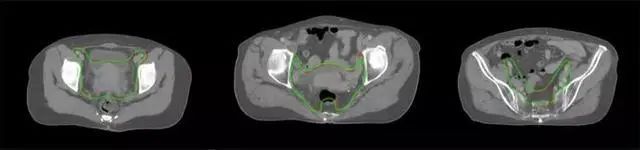

放射治療,簡稱放療,是治療腫瘤主要手段之一,利用放射線破壞照射區(qū)(靶區(qū))的細胞,使腫瘤細胞停止分裂直至死亡,醫(yī)生通常把放射治療形象的比喻為“打靶”,放療前精準勾畫腫瘤靶區(qū)范圍是腫瘤放射治療的關(guān)鍵步驟。傳統(tǒng)的靶區(qū)勾畫醫(yī)生會根據(jù)患者多張CT、MRI影像片憑借經(jīng)驗進行,比較耗時,治療的病人數(shù)量也有限,且靶區(qū)勾畫缺少行業(yè)統(tǒng)一的規(guī)范和標準,無法達到同質(zhì)化,勾畫精確度不理想。

技術(shù)原理

基于深度學(xué)習(xí)人工智能的放療靶區(qū)智能勾畫技術(shù)和自動計劃技術(shù),基于全面的市場調(diào)研和臨床專業(yè)意見,采用獨創(chuàng)的基于小樣本量的人工智能算法,實現(xiàn)放療靶區(qū)和危及器官的快速全自動勾畫。

產(chǎn)品優(yōu)勢

縮短至幾分鐘內(nèi)便可完成,大幅提升了放療效率,且人工智能平臺完成的靶區(qū)勾畫可基本滿足臨床醫(yī)生需求,專家只需審核時細微調(diào)整,可顯著提高靶區(qū)勾畫的規(guī)范化及精準度,讓放療智能化,標準化。可覆蓋食管癌、鼻咽癌、直腸癌、宮頸癌、肺癌等多種病種。